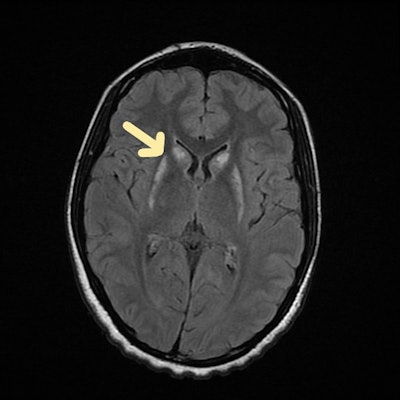

Organophosphate poisoning

Organophosphorus poisoning mainly results in acute neurological dysfunction and respiratory distress, the authors noted in work presented at ECR 2024. Anticholinesterases cause three distinct neurological syndromes following accidental or suicide exposure, such as life-threatening acute cholinergic crisis, intermediate syndrome with cranial nerve palsies, proximal muscular weakness, and delayed organophosphate-induced polyneuropathy.

Organophosphate poisoning. Axial MRI scan shows fluid-attenuated inversion recovery (FLAIR) hyperintensity in caudate and lentiform nucleus of brain.

In these cases, CT shows hypoattenuation bilaterally in the basal ganglia. MRI shows diffusion restriction with symmetrical T2 or T2 fluid-attenuated inversion recovery hyperintensities involving bilateral globus pallidus with extension to the posterior limb of bilateral internal capsules and bilateral cerebellar hemispheres, which indicates acute infarcts.